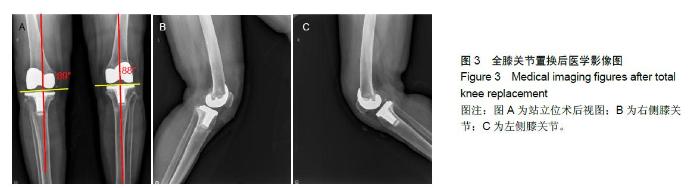

METHODS: Medical image data of patients were collected using CT or magnetic resonance scanning equipment. The three-dimensional reconstruction of the bone was conducted by two-dimensional medical image processing technology. The navigation template was designed by computer-aided design technology. The personalized surgical navigation templates were produced by 3D printing technology, and the clinical total knee replacement was conducted. The postoperative results were evaluated using imageology.

RESULTS AND CONCLUSION: Arigin 3D Pro (Arigin Medical Co., Ltd.) can accurately reconstruct a three-dimensional model of the lower limb bones. The three-dimensional design software Arigin Surgical Templating by their independent research and development can precisely pinpoint related lower limb axis, including limb alignment, rotation axis of the femur and osteotomy reference point. The personalized navigation template we researched and produced for knee surgery fitted tightly with femoral condyle and tibial plateau bone anatomy during operation,

without significant movement. The deviation of patients’ limb alignment was less than 3° after total knee replacement.